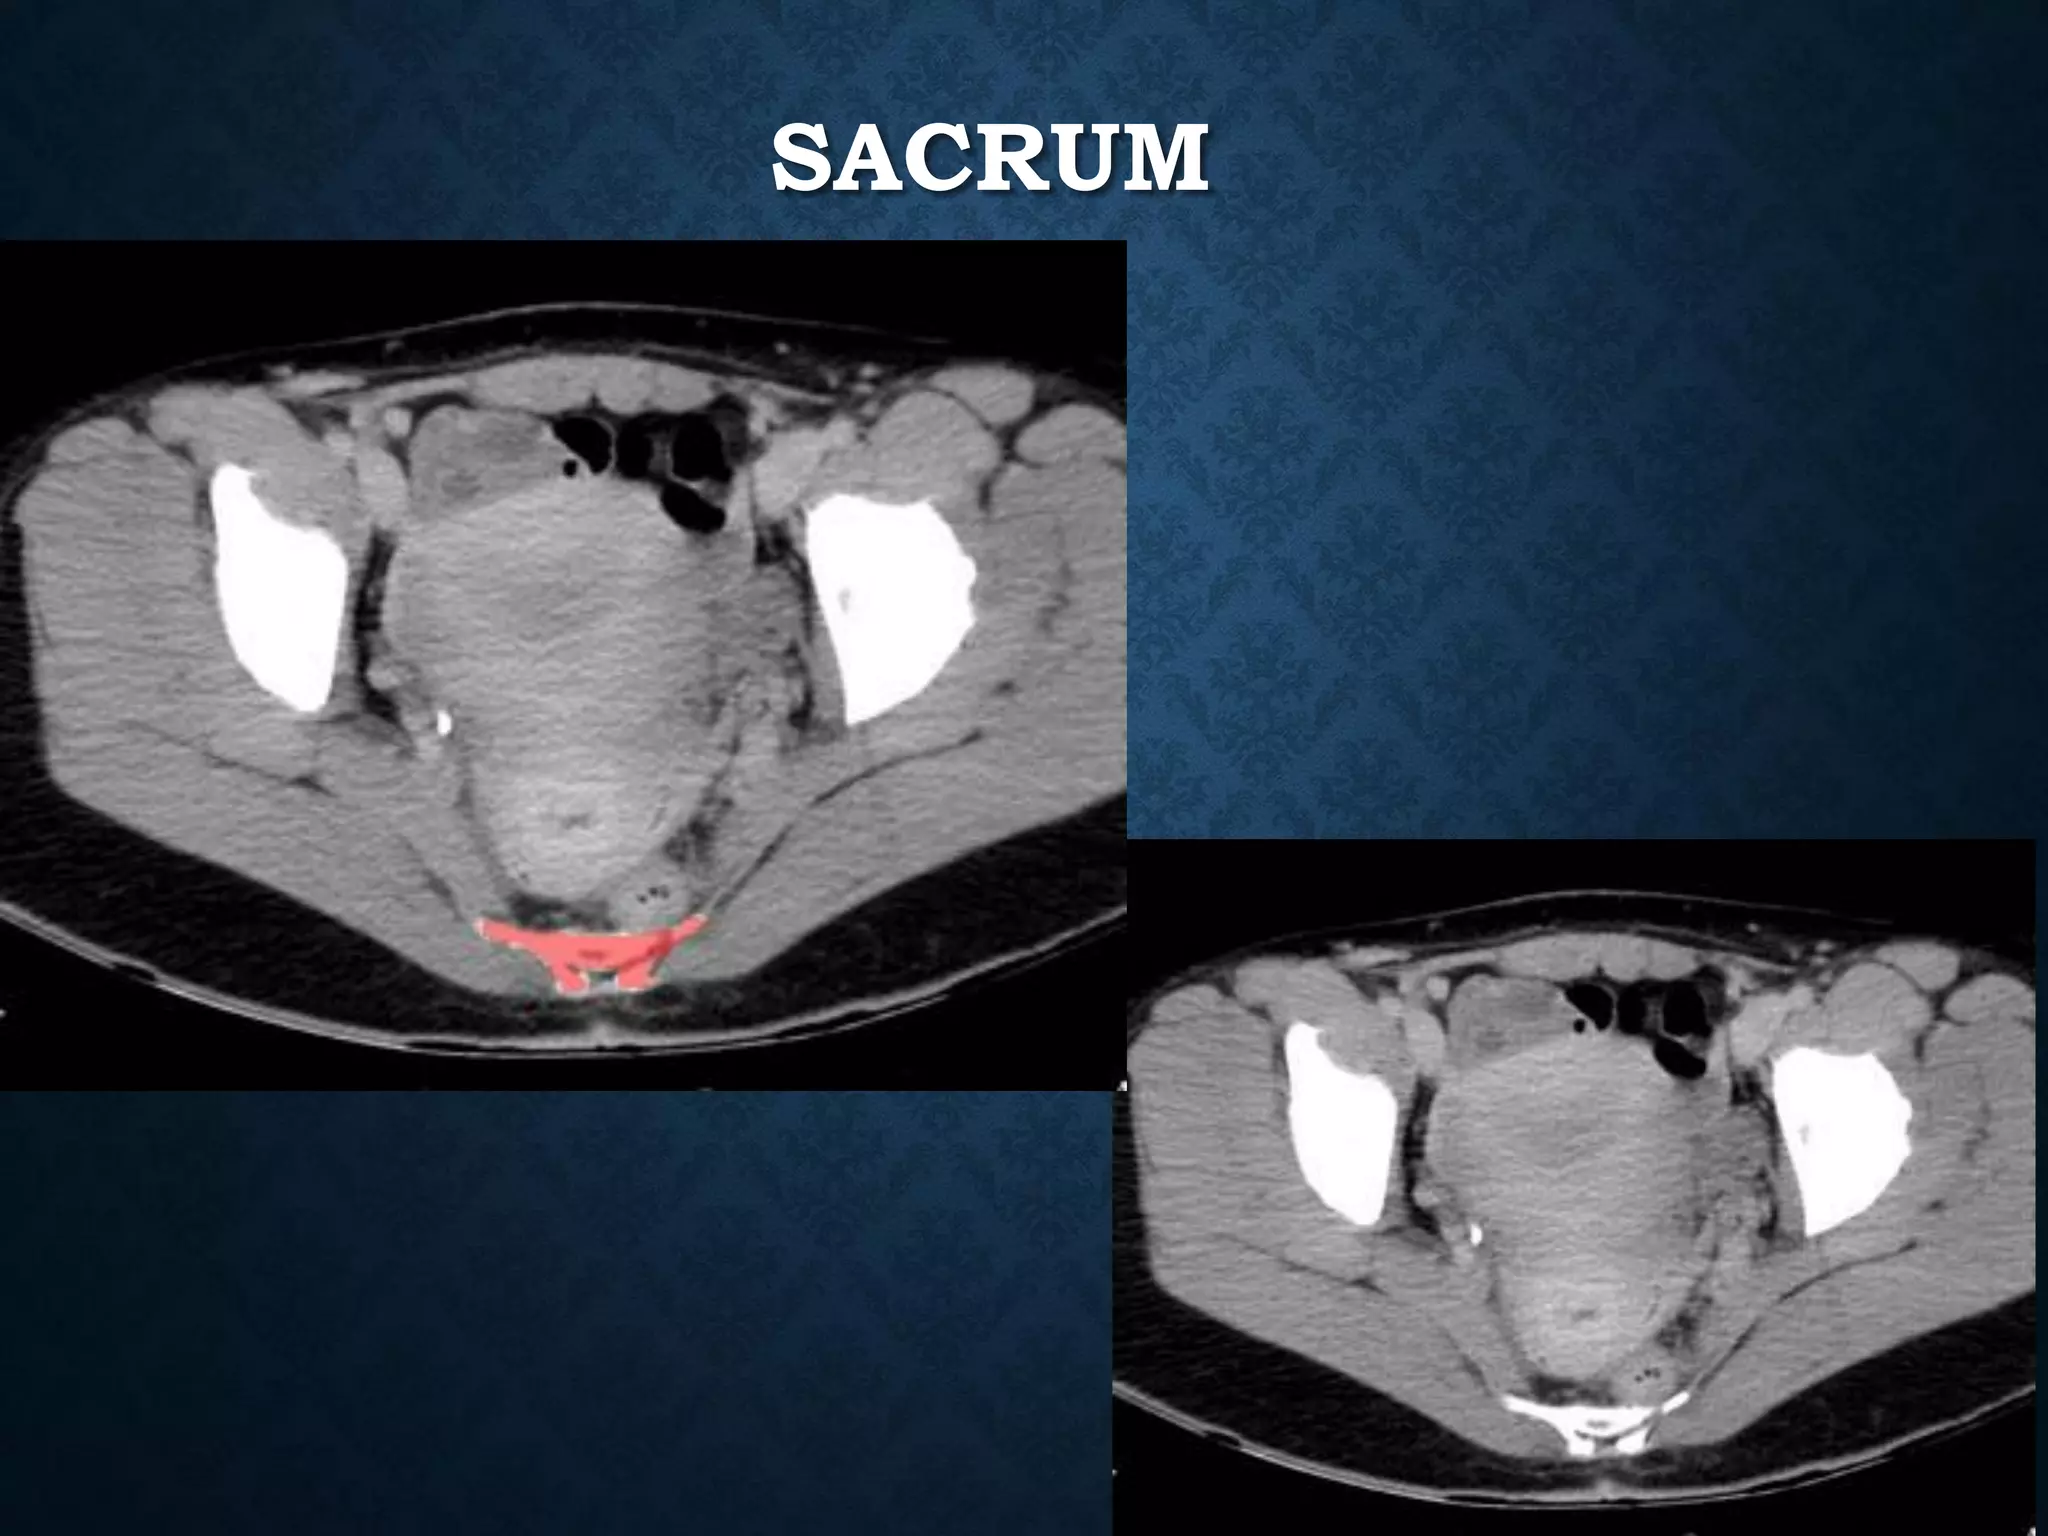

SACRUM

RECTUM- SACRUM